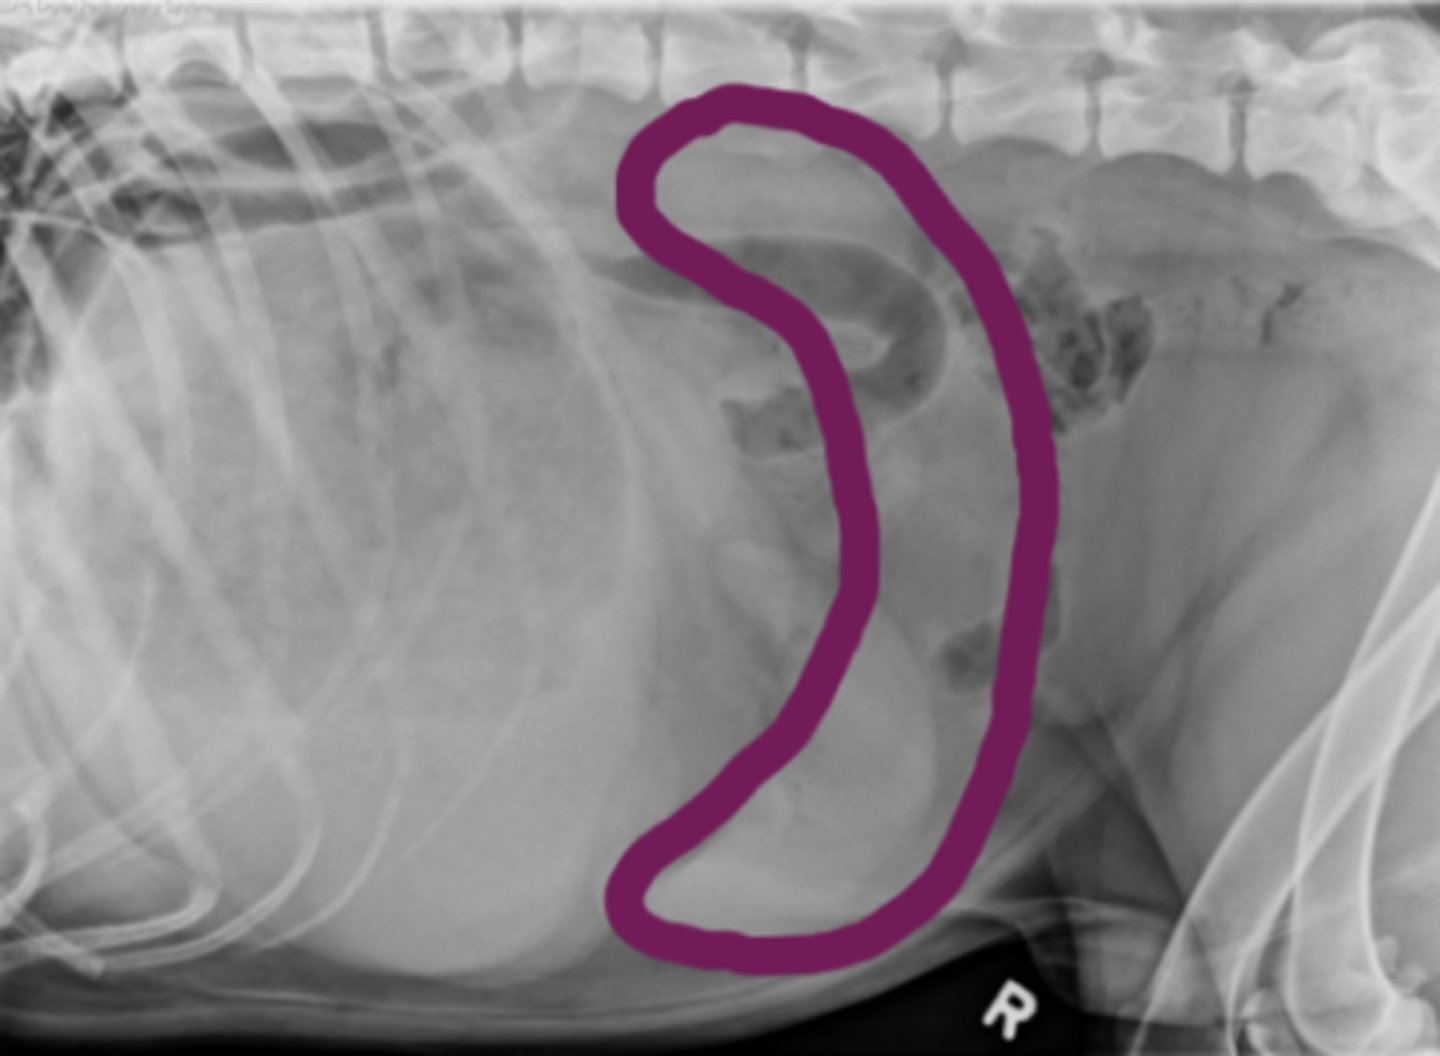

torsión esplénica

(C invertida)

patología: